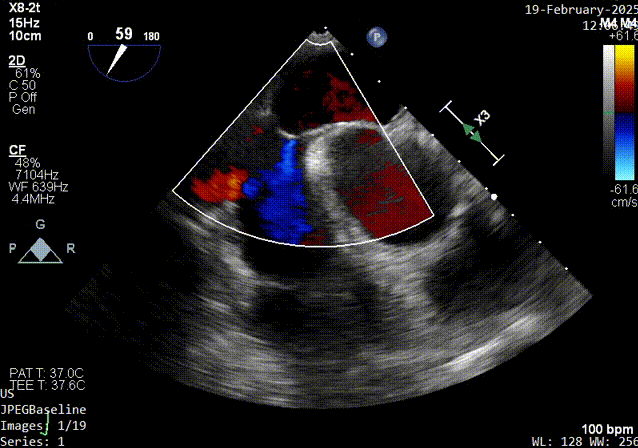

color超声影像

经食道超声:房间隔卵阙窝边缘见卵圆瓣闭合不佳,可见一隧道样缝隙,长约16mm,左房面约1.6mm,右房出口约1.0-2.3mm,X-plane短轴切面而测得宽度约10mm,CDFI可在该处探及左向右过血流。原发隔卵圆瓣厚约1.3mm,继发隔厚度约4.4mm,右房面出口距主动脉根部约7mm,距上腔静脉入口约19mm。